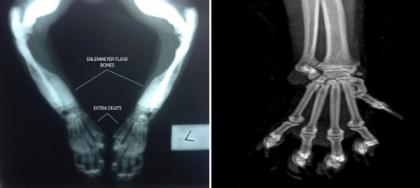

小家伙畸形得厉害,在它的前肢的猫掌上有六趾,而后肢只有五趾。而普通的喵星人通常只有4到5只趾头。并且她没有牙齿。专家们说这只喵的骨头生长地非常快,但她的鼻子却没有时间长到足够的长度以适应缔结组织间骨头的形成。

Lil Bub有自己独一无二的骨头,被称作“锥形瓶”式的骨头。

在左图的X射线中,你可以清楚地看到一只普通猫咪的骨腔,但是右图Lil Bub的X射线中,你可以看到这些钙化的骨头,比普通猫咪的要厚很多。这些就是所谓的“锥形瓶”式的骨头。科学家们希望从中了解到一些具体的基因突变的原因,不仅仅针对猫咪,更是对人类。